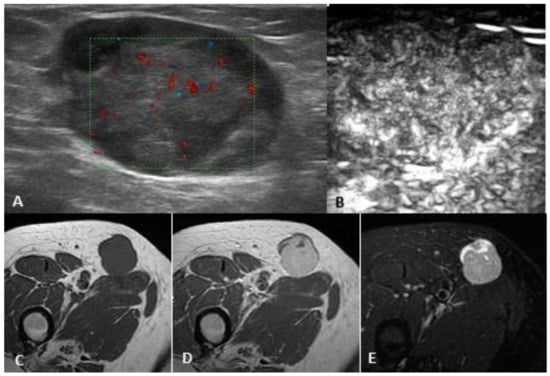

2.2.1. US and Power Doppler Sonography (PD)

2.2.2. CEUS

2.2.3. MRI